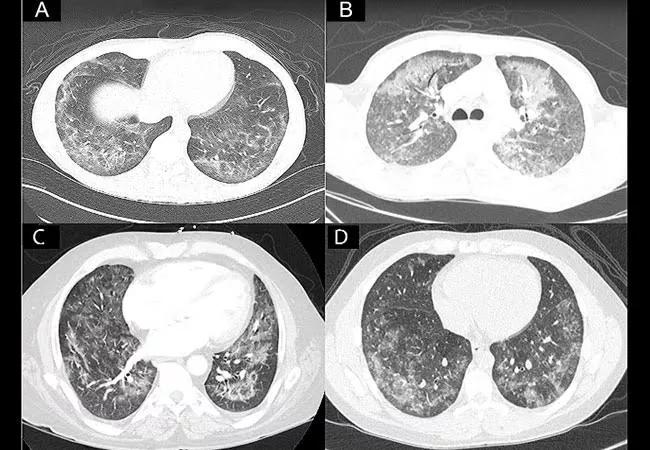

In a recent study published in the American Journal of Clinical Pathology, lung pathologists from Cleveland Clinic report the microscopic findings in lung biopsies from eight patients who developed severe pulmonary illness associated with vaping. This is one of the first case series in the world to examine lung biopsies from patients with vaping-associated lung illness and is the first study on vaping published in a pathology journal. The authors found histologic evidence of acute lung injury in the form of organizing pneumonia and diffuse alveolar damage. In contrast to early clinical reports based on bronchoalveolar lavage findings, there was no evidence of exogenous lipoid pneumonia.

Sanjay Mukhopadhyay, MD (@smlungpathguy), Director of Pulmonary Pathology at Cleveland Clinic, was first author of the study, which includes co-authors from Cleveland Clinic’s Respiratory Institute, Vanderbilt University Medical Center and other institutions. Dr. Mukhopadhyay notes, “Given the current theory that a lipid or oily substance causes lung damage in patients who vape, we were surprised to find that classic features of exogenous lipoid pneumonia were absent in these biopsies. Since lung biopsy findings in vaping-associated pulmonary illness had not been reported at the time we made these observations, we decided that it was important to document these findings given the immense public health importance of this issue.”